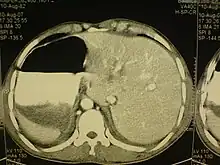

Cet état touche toutes les grandes structures de la cavité thoracique et de l’abdomen. En général, les organes sont simplement transposés par rapport au plan sagittal[1]. Le cœur est situé sur le côté droit du thorax, l’estomac, la rate sur le côté droit de l'abdomen et le foie, ainsi que la vésicule biliaire sur le côté gauche. Le poumon gauche est formé de trois lobes, le poumon droit de deux lobes, tandis que les vaisseaux sanguins, les nerfs, les vaisseaux lymphatiques et les intestins sont également transposés.

Si le cœur est déporté sur le côté droit du thorax, il s’agit d’une anomalie connue sous le nom de situs inversus avec dextrocardie ou situs inversus totalis. Si le cœur reste dans sa position normale, la partie gauche du thorax, il s’agit d’une affection beaucoup plus rare (1 sur 22 000 personnes dans la population générale), désignée par le terme situs inversus avec levocardie ou situs inversus incompletus. Les personnes atteintes de situs inversus avec levocardie ou de dextrocardie sans situs inversus présentent des taux beaucoup plus élevés de malformations congénitales que celles qui sont affectées de situs inversus avec dextrocardie. De plus, les individus atteint de cette malformation avec une levocardie sont des cas qui s'accompagnent souvent de troubles cardiaques[1].